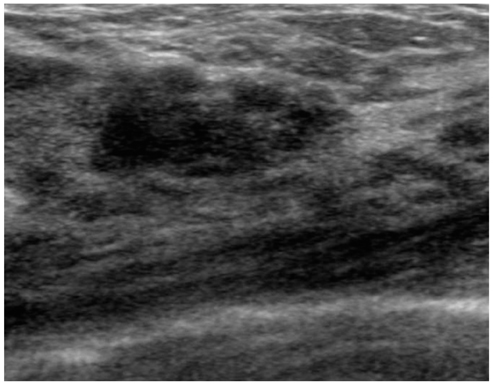

- The purpose of this study is to review various breast diseases in children and adolescents and to illustrate the sonographic findings. We reviewed the cases at our institution in order to identify breast disease in children and adolescent patients who underwent sonography and mammography. Breast disease in children and adolescents included developmental disturbance, infection, benign tumors and inherent defects. In contrast to adults, the radiologic findings of malignant breast conditions in pediatric populations have rarely been reported; however, we show ductal carcinoma in situ with juvenile fibroadenoma and rhabdomyosarcoma. During childhood and adolescence, the recognition and correct identification of physiologic breast development and specific lesions in breast entities on radiologic findings is most helpful in identifying and characterizing abnormalities and in guiding further investigation.